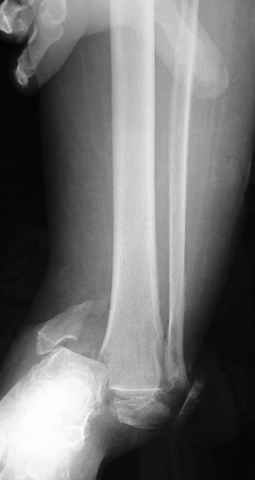

Еще, кстати, о фиксации лодыжки, если уж непременно хочется ее отдельно стабилизировать - при таком характере перелома замечательно должен сработать предложенный проф. Лазаревым с соратниками способ фиксации напряженной V-образной спицей. Опять же, открытая репозиция не нужна, мы делаем непрямую репозицию именно аппаратом. В приложении пример, там перелом малоберцовой куда менее поперечный, чем в данном случае, но все равно получилось закрыто без пластинки.

A propos fibular fixation if one is eager to stabilize it separately. In the fracture pattern a way of closed fixation by V-shaped stressed wire (advanced by colleagues from Moscow, prof. Lazarev A.F. et al.) must be excellent. We use indirect closed reduction by the external fixator. Example attached, that fibular fracture is even more suitable for plating but the wire did the job.